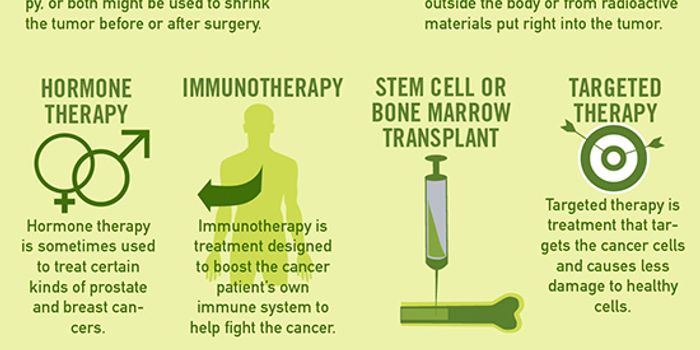

OCT 05, 2017InfographicsCancer touches the lives of most people in the world in one way or another. From family members, friends, or colleagues ...